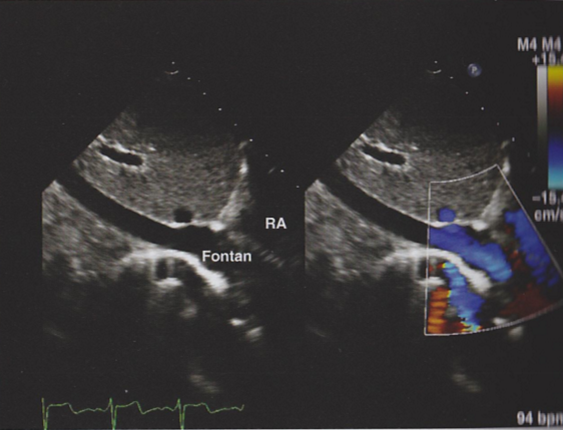

Describe the findings in this image.

Extracardiac conduit seen traveling behind the RA. Good forward flow.